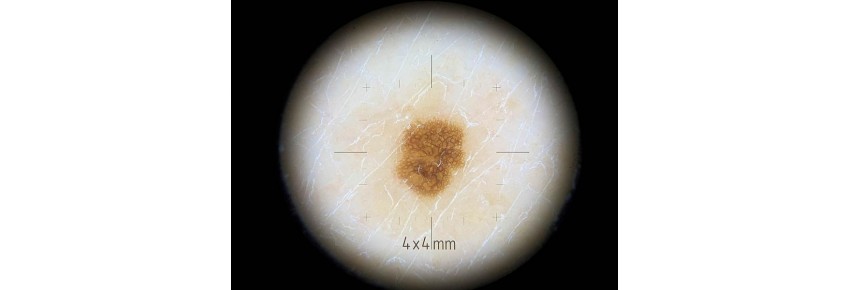

El Adaptador Áreas Difíciles - DL4/DL4W es una herramienta indispensable para el diagnóstico de lesiones cutáneas en áreas del cuerpo de difícil acceso. Gracias a su diámetro compacto de 10mm, este adaptador permite un análisis detallado incluso en espacios reducidos, facilitando el examen de zonas delicadas o angulares.

• Diámetro compacto de 10mm: Permite examinar fácilmente áreas difíciles de alcanzar como los pliegues de la piel o las zonas laterales.

• Retículo de 4x4 mm: La fina retícula incluida ayuda a proporcionar un mapeo preciso durante el examen, particularmente útil para mediciones y análisis detallados.